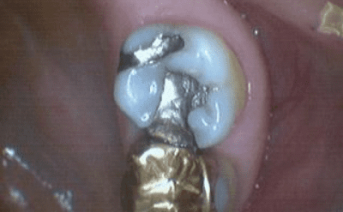

Our composite dental fillings in Atlanta, Georgia, not only fill in cavities, but can treat various cosmetic treatments by filling in teeth that have been damaged or demineralized. Schedule your treatment at Smiles of Atlanta with our dentist, to see if you need a composite dental filling from Dr. Ed Trizzino. Call 770-777-0808 today.